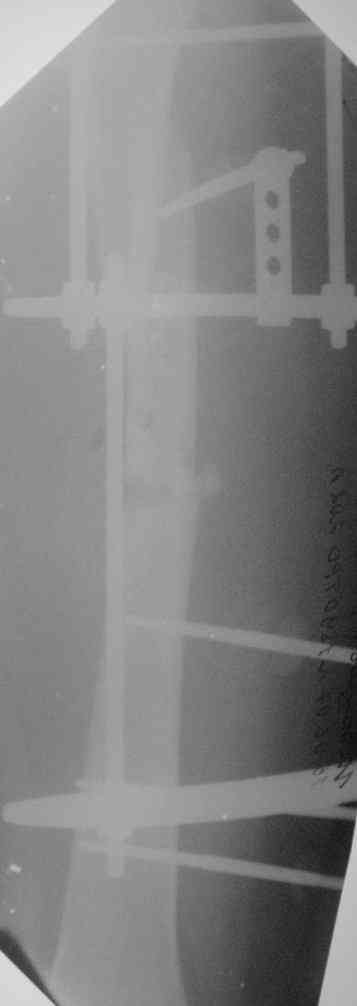

[Ortho] Несросшийся двойной перелом бедра

Молодой человек, 26 л., 6 месяцев назад получил перелом бедра. Вскоре присоединилась

клиника жировой эмболии,

поэтому лечили аппаратом внешней фиксации. На сегодняшний день картина следующая(см.

приложение) В обсуждении предложены следующие варианты: 1) макс.дистракция в аппарате с

переходом на дистрактор таз-бедро, штифтование сплошным титановым 12мм(более нет)

гвоздем с рассверливанием.2) дистракция в аппарате, окрытый синтез полым 10 мм гвоздем с

минимальным рассверливанием.3) снять аппарат, пластиковая повязка, подожать 2 мес.,

вернуться к обсуждению. Краеугольными вопросами дискуссии стали: 1)полый или сплошной?

2)открыто или закрыто (у нас нет ЭОПа, но большиство штифтований делаем закрыто)? 3) в какой

срок после снятия аппарата можно штифтовать? Дорогие коллеги помогите определиться с

тактикой, надеемся на Ваше компетентное, независимое мнение. Спасибо.